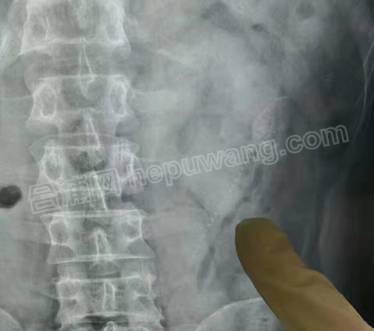

因活物入体的病例较为少见,且病人持续高烧、心率过快、血压偏低,情况极为紧急!暨南大学附属第一医院外科医生通过腹部DR检查确定泥鳅在体内的位置后,紧急制定了手术方案,于12日凌晨1点开始手术。此时,距离两条活鱼进入体内的时间已过去了24个小时。

通过腔镜微创,其中一个目标物很快被确定位置,因在体内缺氧,这条泥鳅已经没了生机。医生很顺利地将这条长15厘米左右、宽3厘米左右的泥鳅从患者体内取出。

医生迅速对病人的整个腹腔进行“地毯式搜索”,最终在患者腹部左上侧、距离肠壁溃烂口不远处找到了这条长约10厘米、宽2厘米的死泥鳅,并将其完整取出。